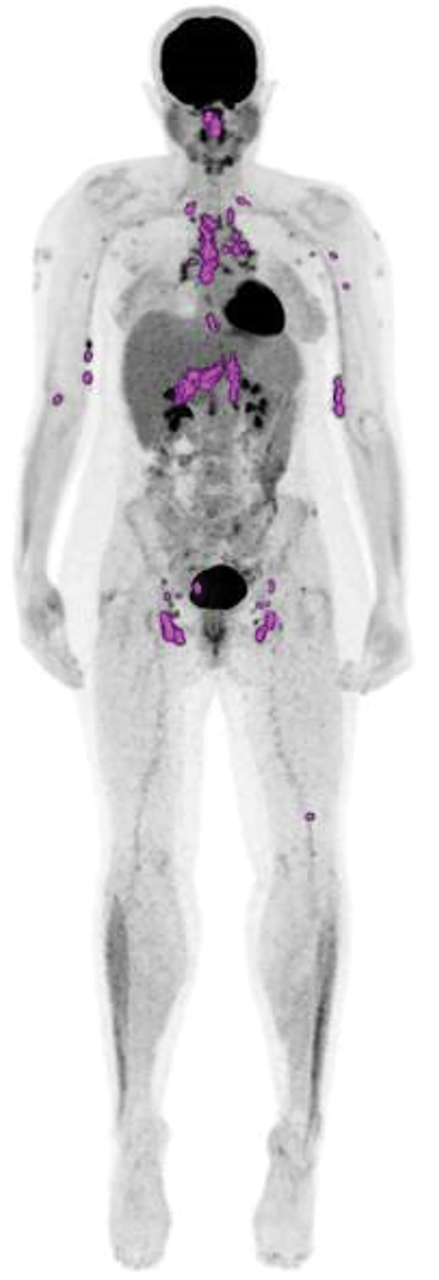

La sarcoïdose est une maladie systémique granulomateuse qui peut, en dehors de la localisation médiastinale et pulmonaire la plus fréquente, atteindre l’œil (uvéite), la peau, le système nerveux central, le cœur, le rein. Les adénopathies épitrochléennes, bien que rares, sont très caractéristiques.